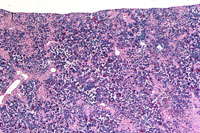

A higher magnification of hepatic erythroleukemia.

Examples of erythroleukemia in a Tg.AC mouse.